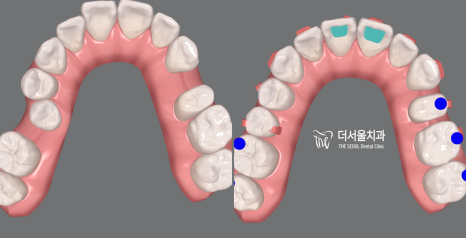

위 사진에서 볼 수 있듯이

약간 뻐드러진 치아 배열과 우식,

그리고 제위치에서 벗어난 소구치 때문에

여러 고민이 많으셨던 분인데요.

이분께서는 교정과 우식 제거를

동시에 원하고 계셨던 상태였습니다.

따라서 더 서울에서는 충치치료 먼저 진행한 뒤,

치열 개선을 시작하는 방법으로 돕기로 했는데요.